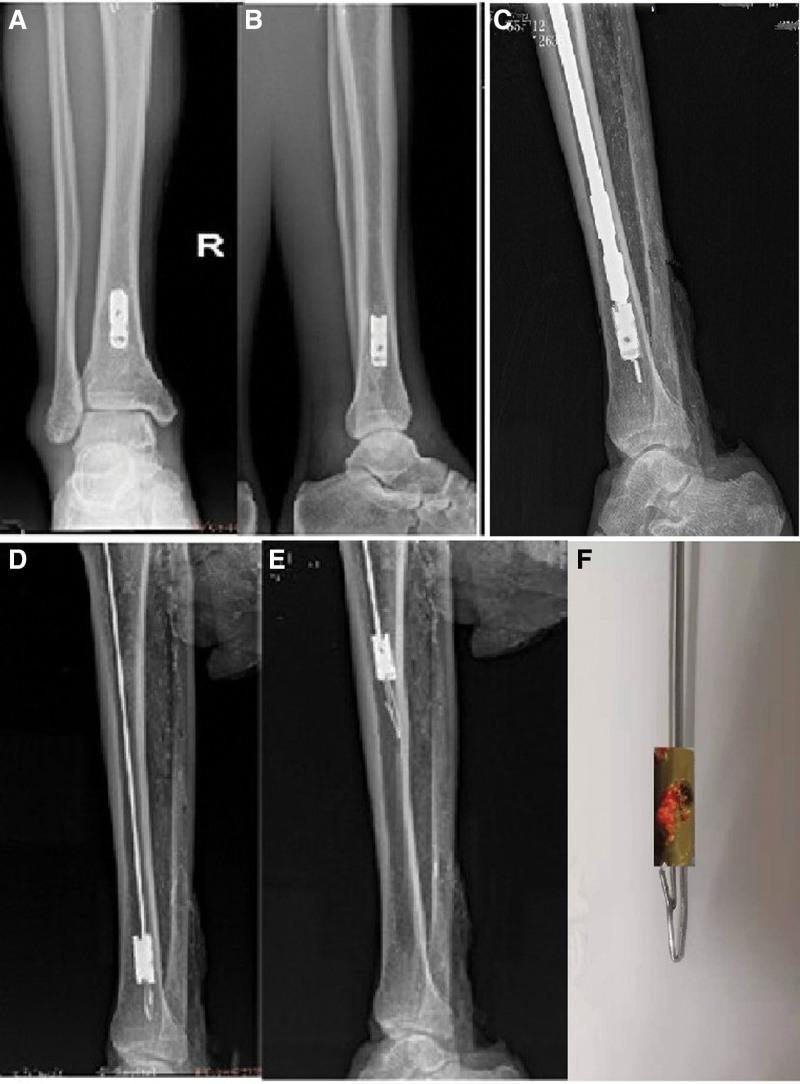

Successful and minimally invasive extraction of a broken distal end of an intramedullary nail is challenging. This study introduces a simple and reproducible technique for the extraction of broken cannulated intramedullary nails using a novel minimally invasive broken nail extractor. Five amputated adult lower-leg specimens were used to create models of the broken distal end of the cannulated intramedullary nails remaining in the medullary cavity of the distal tibia. Two orthopedic resident physicians with experience in tibial intramedullary nail implantation were selected to blindly extract the broken intramedullary nail using the novel minimally invasive broken nail extractor. The extraction outcome was assessed. The broken nail extractor was applied to 3 patients with broken intramedullary nails remaining in the medullary cavity of the distal tibia. In the lower-leg specimens, the extraction success rate was 100%, the median number of extraction times was 1.9 (range 1-3.5), and the median duration of extraction was 38 s (range 20-52 s). All the broken intramedullary nails in the 3 patients were successfully extracted without complications related to the surgery. The study shows that our technique is simple, reproducible, and has a high extraction success rate, but more case applications are needed to verify its effect.

成功且微创地取出髓内钉的折断远端是具有挑战性的。本研究介绍了一种使用新型微创断钉取出器取出折断的空心髓内钉的简单且可重复的技术。使用 5 个截肢成人小腿标本来创建残留于胫骨骨髓腔中的空心髓内钉的折断远端模型。选择 2 名具有胫骨髓内钉植入经验的骨科住院医师,使用新型微创断钉取出器盲目取出折断的髓内钉。评估了取出结果。该断钉取出器应用于 3 例残留于胫骨骨髓腔中的折断髓内钉的患者。在小腿标本中,取出成功率为 100%,中位数取出次数为 1.9(范围 1-3.5),中位数取出时间为 38 秒(范围 20-52 秒)。3 例患者中的所有折断的髓内钉均成功取出,无与手术相关的并发症。该研究表明,我们的技术简单、可重复且取出成功率高,但需要更多的病例应用来验证其效果。